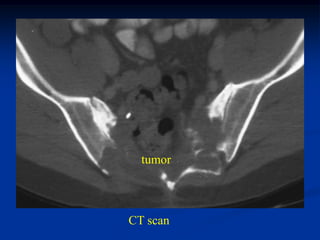

Case #222                       CT scan

65 year female with chordoma sacrum and buttock

tumor

Axial T-2 MRI

Axial T-2 MRI at higher level

femur

Sagittal T-2 MRI

Photomic